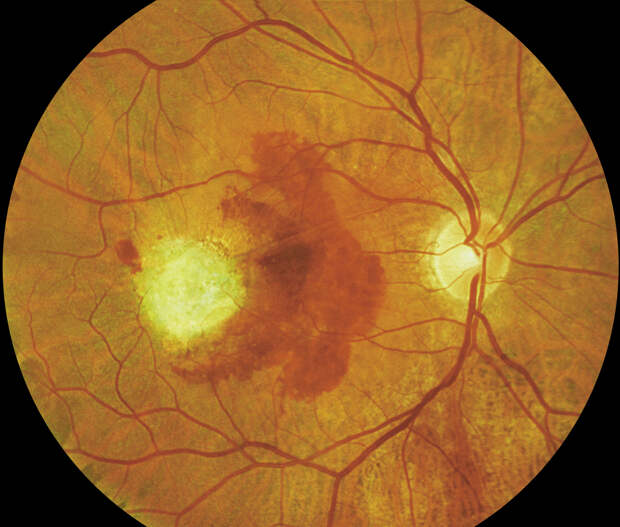

При ВМД снижается острота зрения, пациенту становится трудно читать и распознавать лица людей, а также определять расстояния. Особенно страдает центральное зрение: больной может видеть перед собой тёмное пятно и различать предметы только периферическим зрением.

Есть сухие формы макулодистрофии, но существует и влажная форма, когда под сетчатку через повреждённые пигментные эпителии прорастают неполноценные сосуды, которых там быть не должно. Они пытаются взять на себя функции отмирающих сосудов, но вместо этого вызывают осложнения: могут кровоточить и давать отеки. При влажной, отёчной форме ВМД острота зрения резко снижается, и человек может ослепнуть буквально в одночасье.